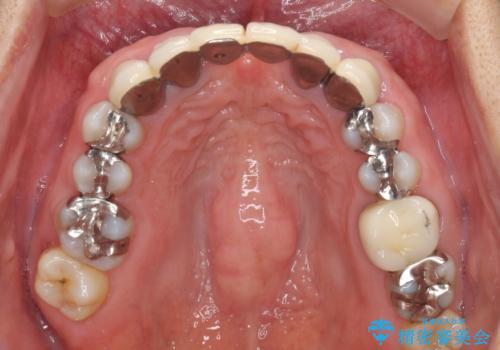

金属を使用した前歯のブリッジや奥歯の銀歯は全てオールセラミッククラウンまたはセラミックインレーとし、左下の奥歯はインプラントにより治療を行うこととしました。

遠方からの来院であったので、1回の治療時間を長めにし、できる限りの処置を集中して行うことで、来院回数を減らすことができました。

初診カウンセリングを含めて13回の通院で治療を終えることができ、患者様には大変満足していただきました。